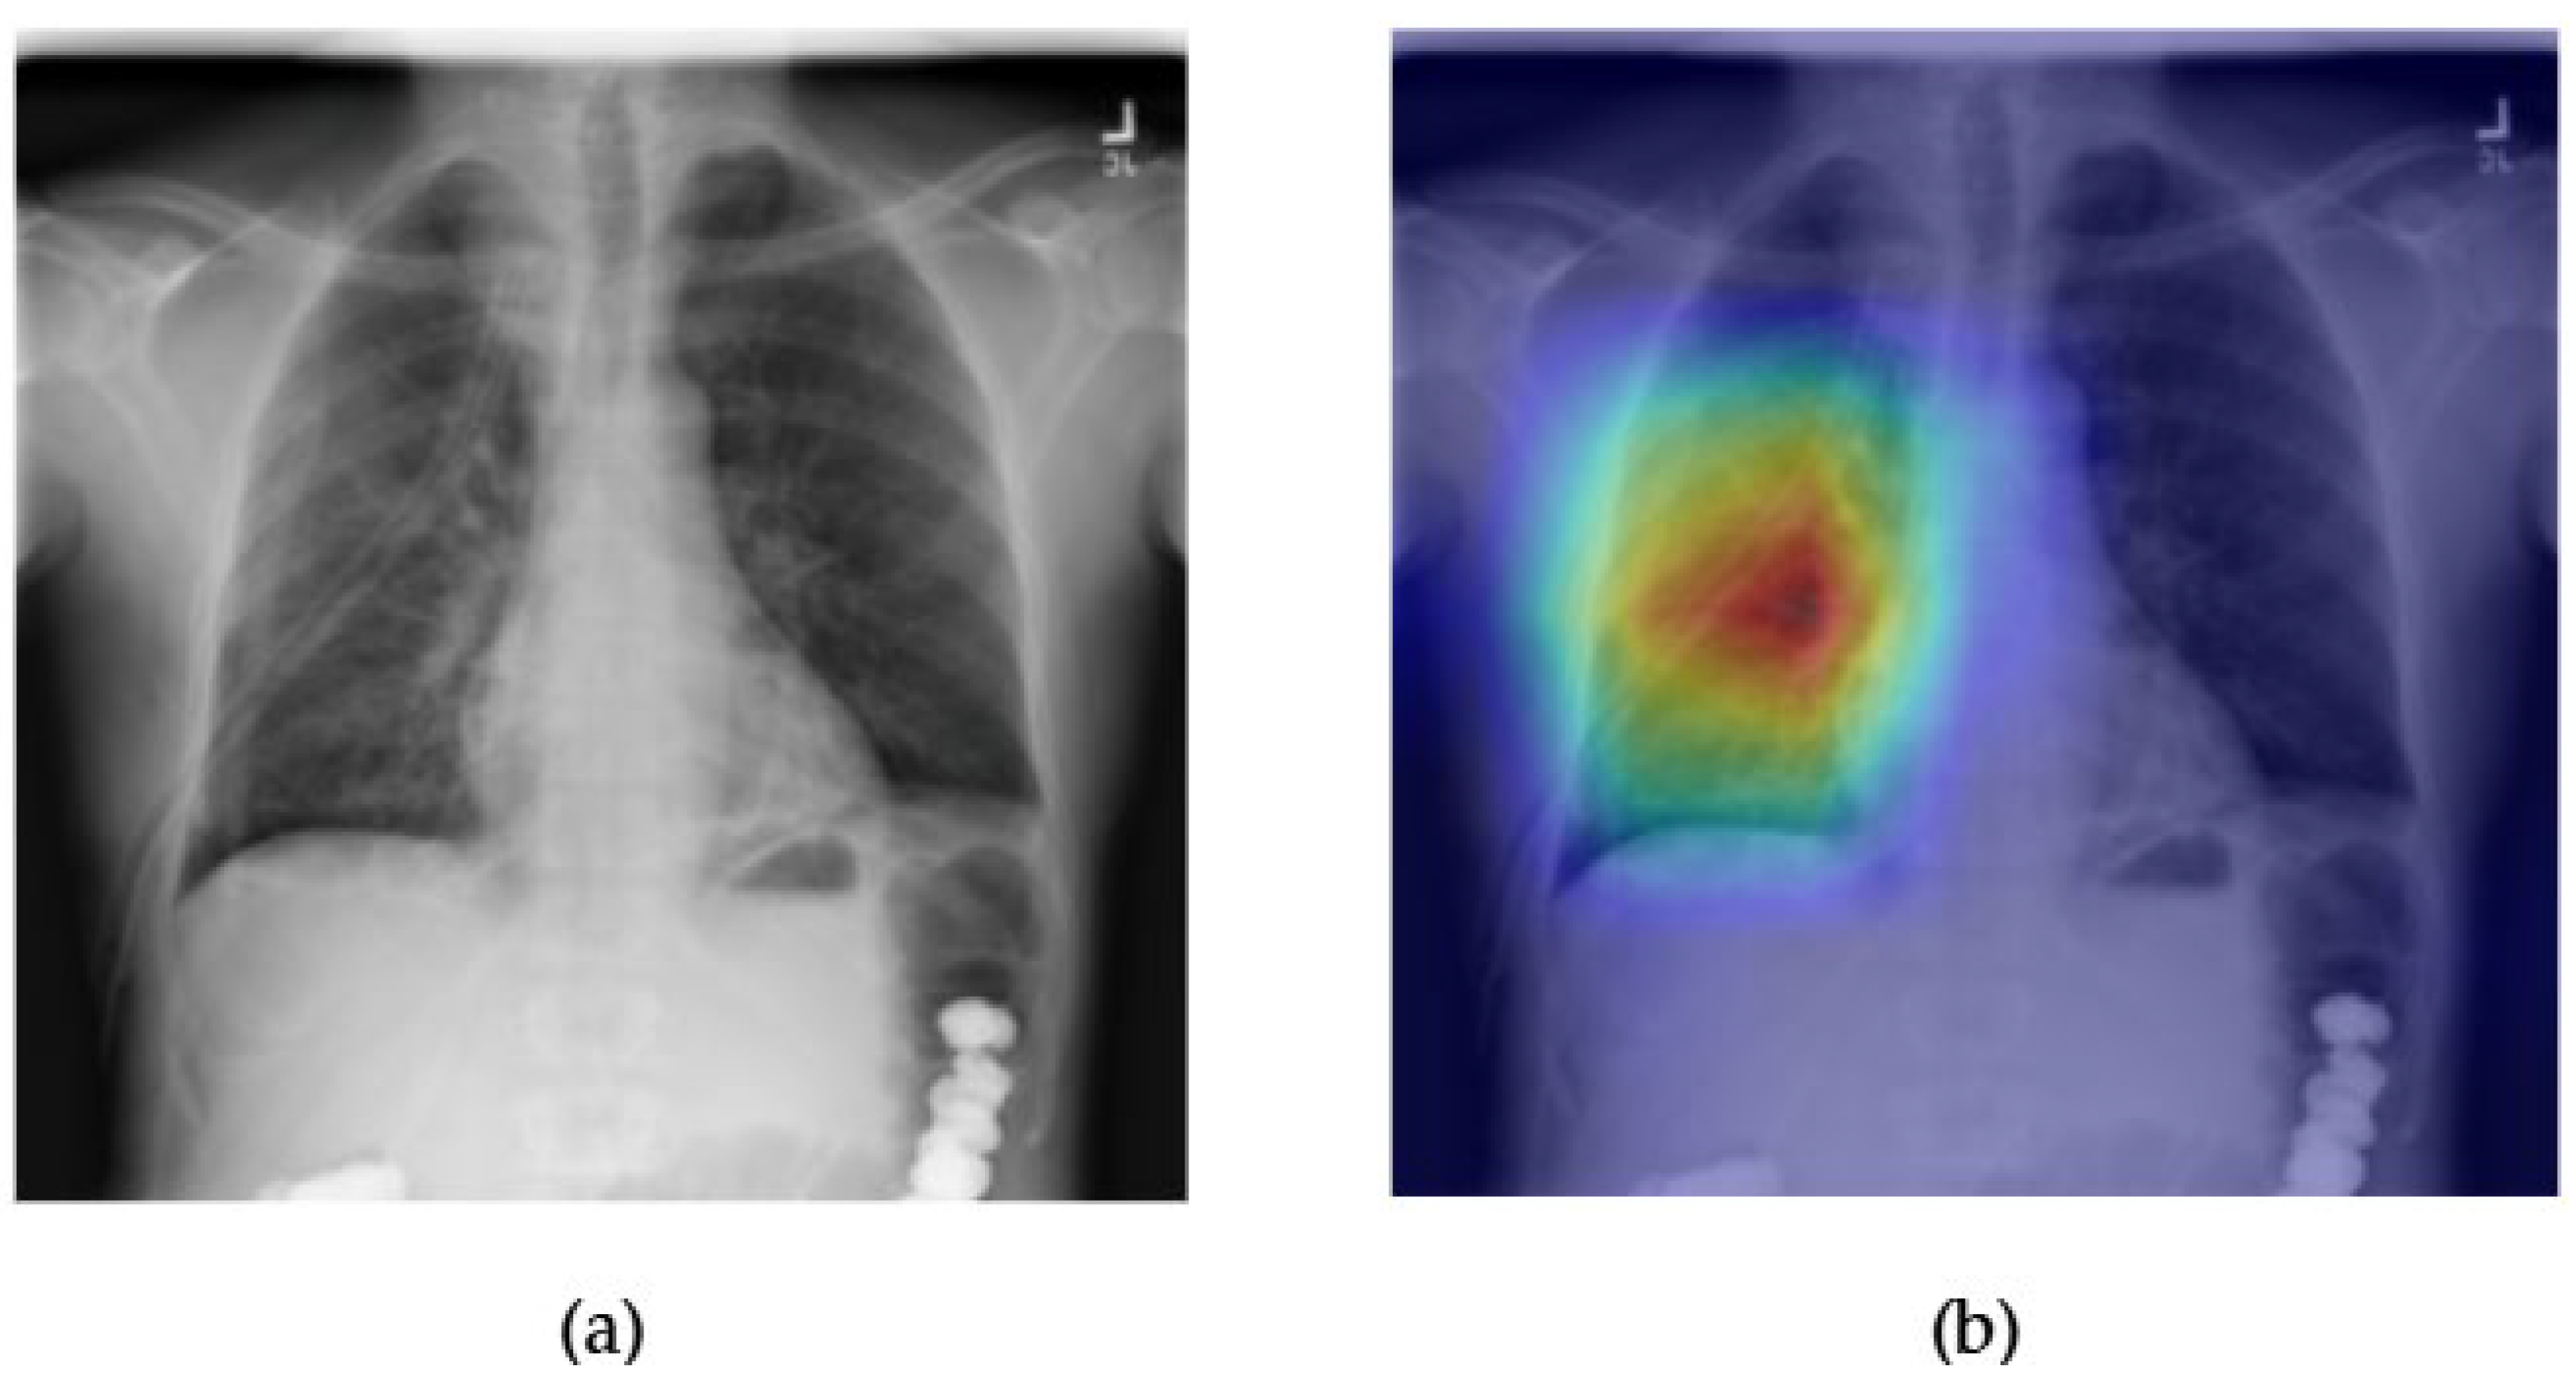

- Although our Grad-CAM-based explainability provides useful localization cues, it is inherently limited by its post hoc nature and reliance on gradient flow from the final convolutional layers. Future research could incorporate advanced interpretability techniques such as Layer-wise Relevance Propagation (LRP), Integrated Gradients, or attention rollouts in Transformers, which may offer a more complete understanding of model reasoning.